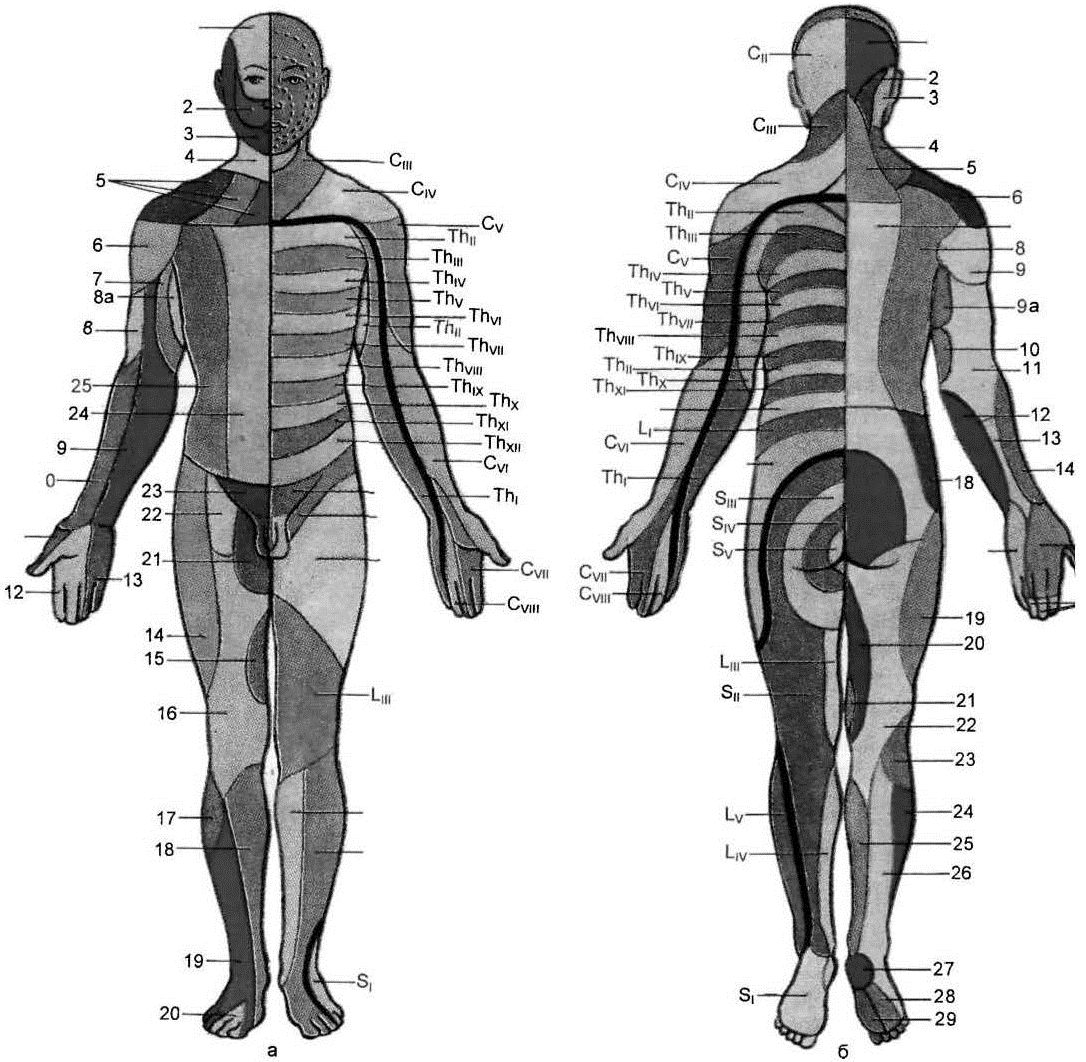

Схема чувствительных зон новой коры мозга